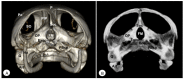

Anatomical Description of Loggerhead Turtle (Caretta caretta) and Green Iguana (Iguana iguana) Skull by Three-Dimensional Computed Tomography Reconstruction and Maximum Intensity Projection Images

The growing interest in reptiles has posed a challenge to veterinary clinicians due to the lack of a standardized system to perform anatomical studies similar to those used for dogs and cats. In this paper, we have attempted to describe, employing computed tomography and subsequent three-dimensional reconstructions, the normal anatomical features that comprise the skulls of two species of reptiles: the loggerhead turtle (Caretta caretta) and the green iguana (Iguana iguana). Computed tomography (CT) and subsequent image processing allowed the identification of the bony structures that comprise the head of these species. As a result, and based on previous articles, we propose the most significant anatomical differences and similarities between these species.